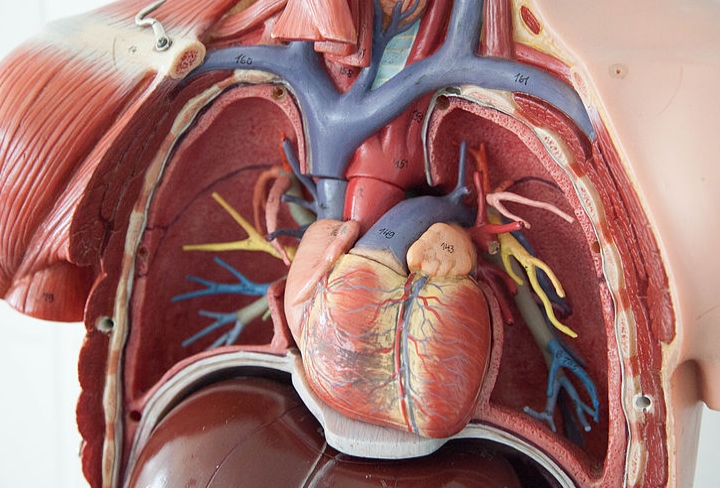

오른쪽 가슴 통증 원인 질환 2. 폐 질환

폐암, 흉막염, 자연기흉 등이 원인이 되어 나타날 수도 있습니다. 흡연자, 불규칙한 생활을 하거나 하는 사람은 아무래도 폐가 약할 수 있습니다. 그리고 10~30대의 마른 체형의 남성에게서는 자연기흉이 나타날 수도 있습니다.

폐 질환으로 인해 오른쪽 가슴 통증 나타나는 경우는 욱신거리는 통증과 가래를 동반한 기침 그리고 숨쉬기 괴롭고 힘든 증상이 나타납니다. 이런 경우는 바로 내과나 호흡기내과 등에서 진찰과 치료를 받아야 합니다.